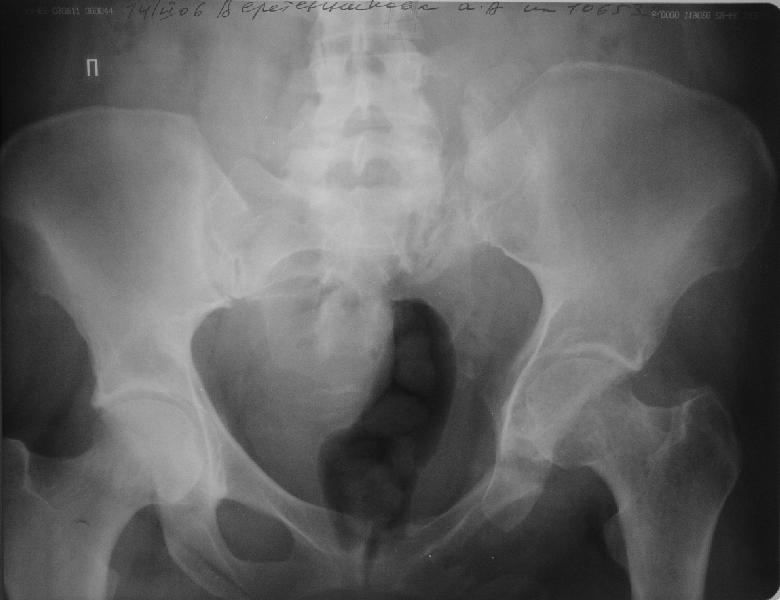

Прооперировали молодую девушку 32 лет спустя 9 мес после травмы. Имелся стойкий болевой синдром, неопороспособность левой н/конечности, моторные и сенсорные нарушения в левой голени и стопе, патологическая подвижность левой половины таза. Первым этапом закрыто в аппарате исправили деформацию ( в течении 2,5 нед). Вторым закрытое введение илиосакральных винтов в крестец (канюллированные 7,2 мм Chm) + туннелизация зоны псевдоартроза спицама Киршнера, реконструкция передних отделов таза, накостный остеосинтез . Аппарат частично демонтирпован, оставлена "передняя рама" После устранения деформации отмечен регресс неврологической симптоматики, уменьшение болевого синдрома. Интересующие вопросы: 1. Прогноз для сращения псевдоартроза крестца. 2. сроки нагрузки весом левой половины таза. Буду очень признателен за ваши мнения по этому поводу.A female 32 y.o. admitted to our unit 9 months after initial injury with pain, inability to bear weight at the left lower limb, sensor and motor disturbances in the left foot and tibia, with mobility of the left hemipelvis.At first closed reduction was performed by an external fixator within 2,5 weeks. After correction her pain decreased and some neurological progress was achieved. Now two iliosacral screws 7,2 mm were inserted, and anterior lesion was fixed by a plate. External fixator was partially unmounted, only anterior frame left in place.Images attached.How would you evaluate chances of healing of the sacrum with the current position?When would you allow weight-bearing of the left leg?THX in advance.

Мне нравится ваша закрытая репозиция девятимесячного ложного сустава, не знаю насчет туннелизации, но шурупы в 7.2 это серёзная конструкция. При стабильной фиксации крестец должен срастись, только я бы держал передний фиксатор до шести недель, костыли, а полную нагрузку разрешить через 12 недель.